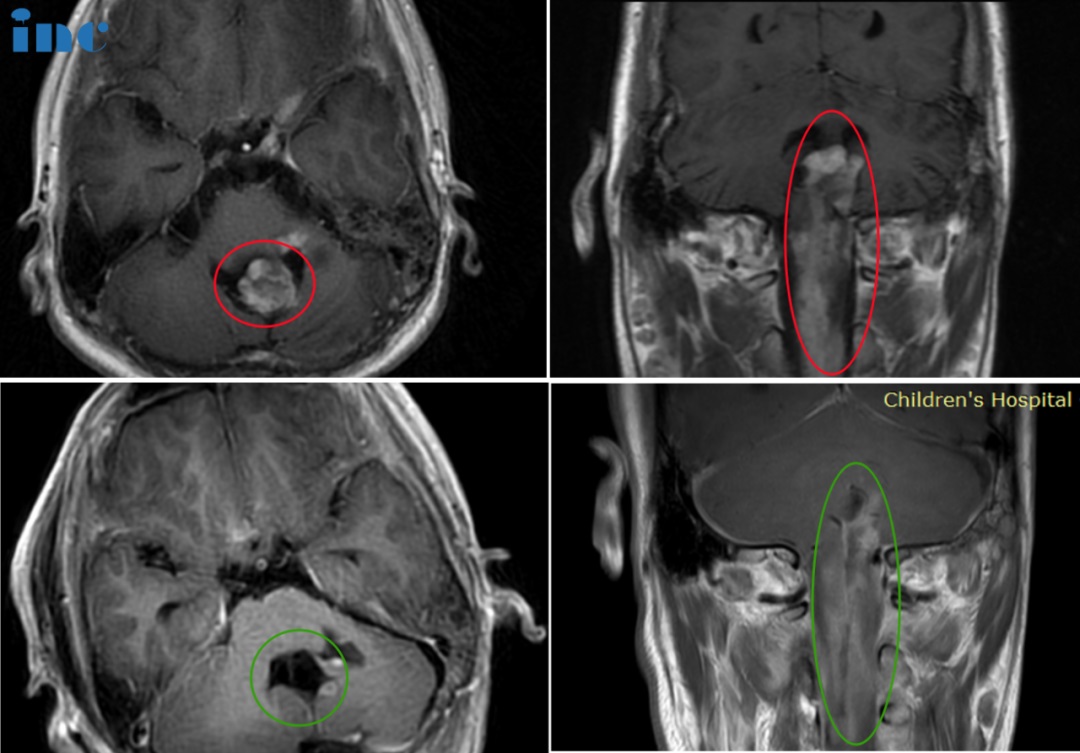

50岁女性-延髓海绵状血管瘤

28岁女性-脑干延髓海绵状血管瘤

19岁男孩-延髓海绵状血管瘤

32岁男性-延髓海绵状血管瘤

30岁女性-延髓-颈髓海绵状血管瘤